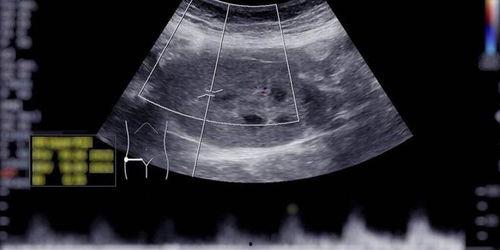

接下来,咱们聊聊B超。B超,全称超声波检查,是一种无创、无辐射的检查方法。它通过发射超声波,探测人体内部器官的形态、大小和位置,从而帮助医生诊断疾病。

首先,西瓜和黄瓜都是水分含量很高的水果,吃下去后,大部分水分会被身体吸收,不会在体内形成大量气泡。其次,即使有少量气泡,B超设备也有强大的滤波功能,可以过滤掉这些干扰信号,保证检查结果的准确性。